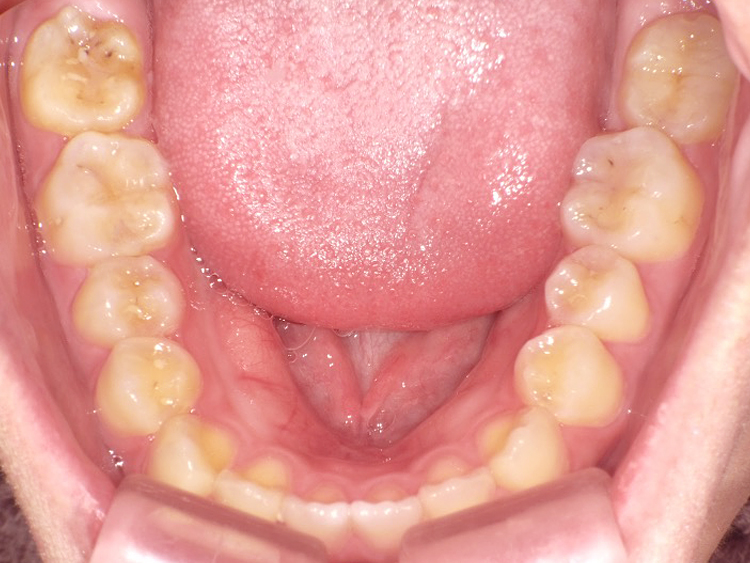

症例3

Before

After

| 主訴 | 上下の歯のガタガタを治したい |

|---|---|

| 年齢 | --- |

| 治療期間 | 約10ヶ月 |

| 治療内容 | インビザラインiGoで上下顎の治療。 狭まっていた歯並びを広げることで、 ガタガタに並んでいた歯を綺麗に並べた。 |

| 治療費 | ¥517,000(税込)+月額調整料 |

| 治療のリスク | 歯と歯の間を削ることでスペースを確保するので、 場合によっては歯が染みる症状が出ることがある。 |